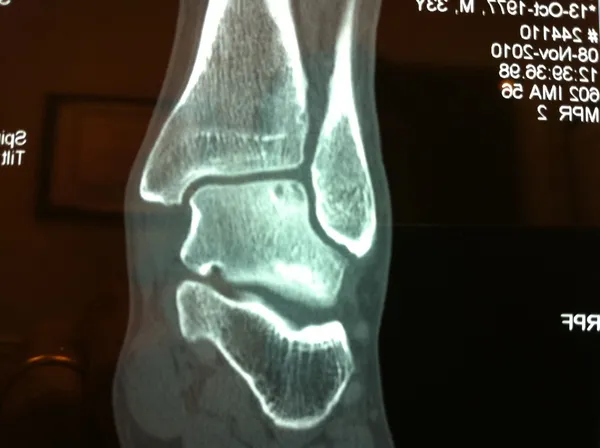

CT and MRI OCD Talus